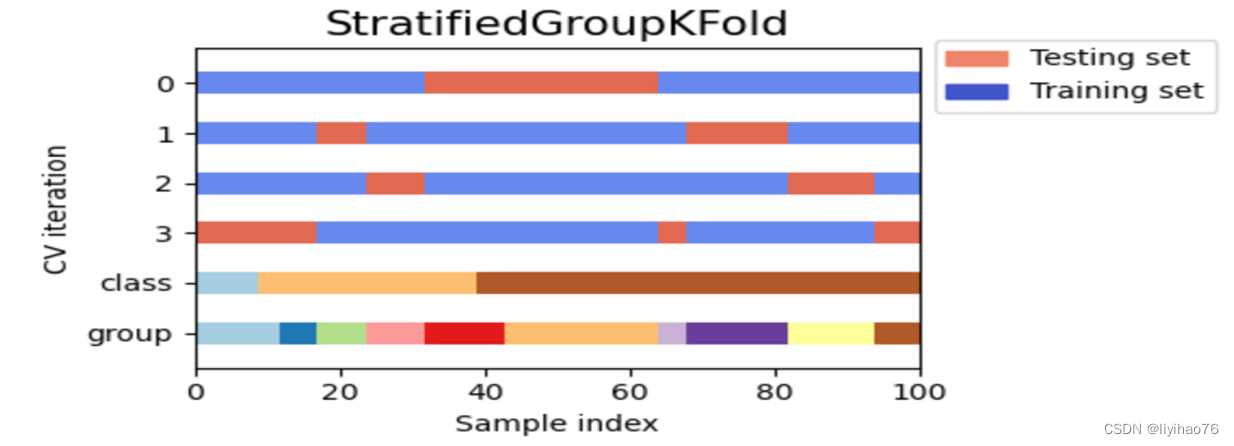

- StratifiedGroupKFold在划分数据集时,不仅要考虑划分后的数据集与原数据集的比例大致相同,还要保证同一组的数据不能同时出现在训练集和验证集中。 我们在比赛中使用了StratifiedGroupKFold交叉验证方法,取得了良好且稳定的性能结果。